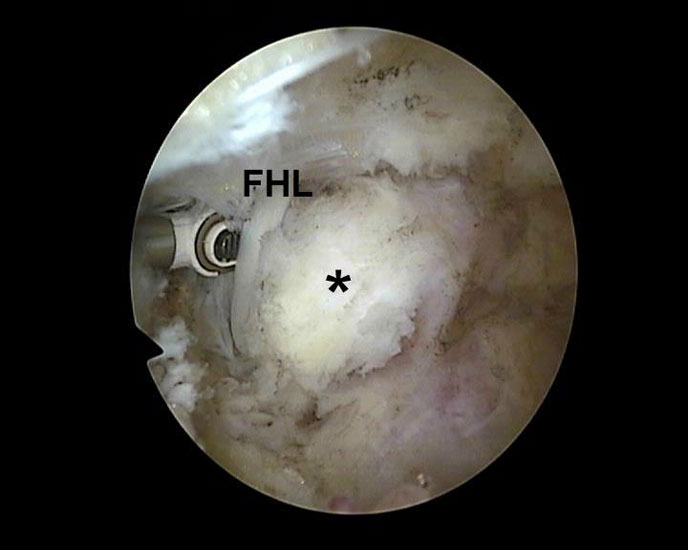

Abbildung Nr. 17 und 18, Video Nr. 3

Das arthroskopische Verfahren eignet sich auch zur Resektion multipler Ossikel (*) und Osteophyten (O). Hier ist der intraoperative Einsatz eines Bildverstärkers unabdingbar, um keine Knochenfragmente im Weichteilgewebe zu übersehen. Zur Osteophytenresektion können problemlos kleine Flachmeißel über die Arthroskopiezugänge verwendet werden (rechte Seite, m= medial, l= lateral, FHL=Flexor hallucis longus-Sehne).